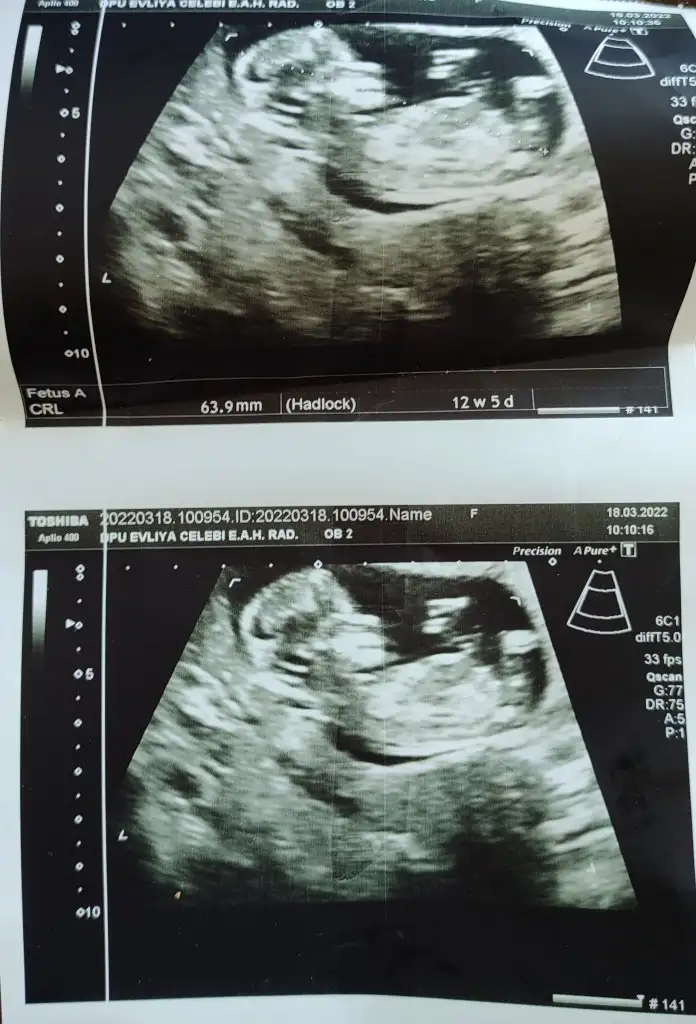

canım prenses gibi, sen ne hissediyorsunMerhaba burda 12 haftalıktı hala cinsiyet göremedi doktorlar ben de bi tahmininizi alabilirim :) teşekkürler şimdiden.Pasha22